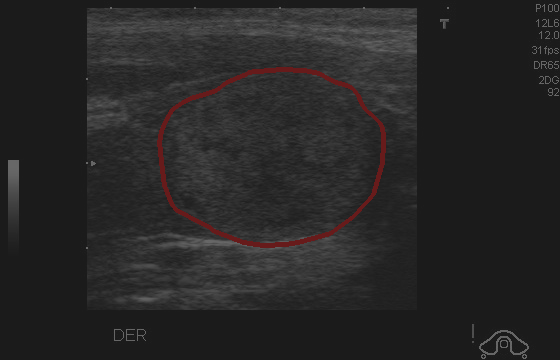

Object Movement

MRI OmniMedVQA Disease Diagnosis

Object Movement - L0 (Original)

L0

L0 (Original)

Question

What is the visual finding in this image?

A Rotator cuff tear B Plantar fascia pathology C Bunion D Golfer's elbow

Ground Truth: B. Plantar fascia pathology